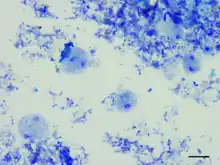

| Dientamoeba fragilis, in a specimen prepared using the Kohn stain | |